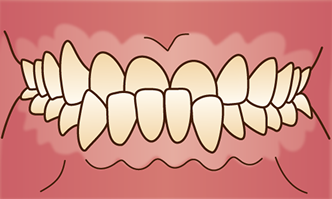

過蓋咬合

4. かがい咬合

上の歯が下の歯を大きく覆うように深く噛み合っている状態を指します。

この噛み合わせでは、下の歯が上の歯茎に当たって刺激し、口内炎を引き起こすことがあります。

また、前歯が常に露出しやすくなることで乾燥し、虫歯の原因になることもあります。

さらに、口腔内の体積が少なくなることで舌が後退し、いびきや睡眠時無呼吸症のリスクが高まるほか、食いしばりが強くなり顎関節症のリスクが高まることもあります。